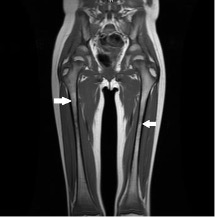

A repeat MRI scan of the bilateral lower extremities was performed because of the inability to obtain the previous MRI scan. Results showed bilateral low T1 and high T2 signal involving the metaphyses of the femurs, tibias, and fibulas (Figure 2). During the workup, the biopsy taken during the patient’s dental surgery returned results significant for a pyogenic granuloma caused by Actinomyces.